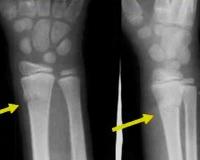

• Рентгенография. Это базовое исследование, позволяющее выявить общие и поднадкостничные переломы, но в случае эпифизиолиза может дать мало информации. В зависимости от степени поражения делается рентген костей предплечья, запястья или локтевого сустава в двух проекциях.